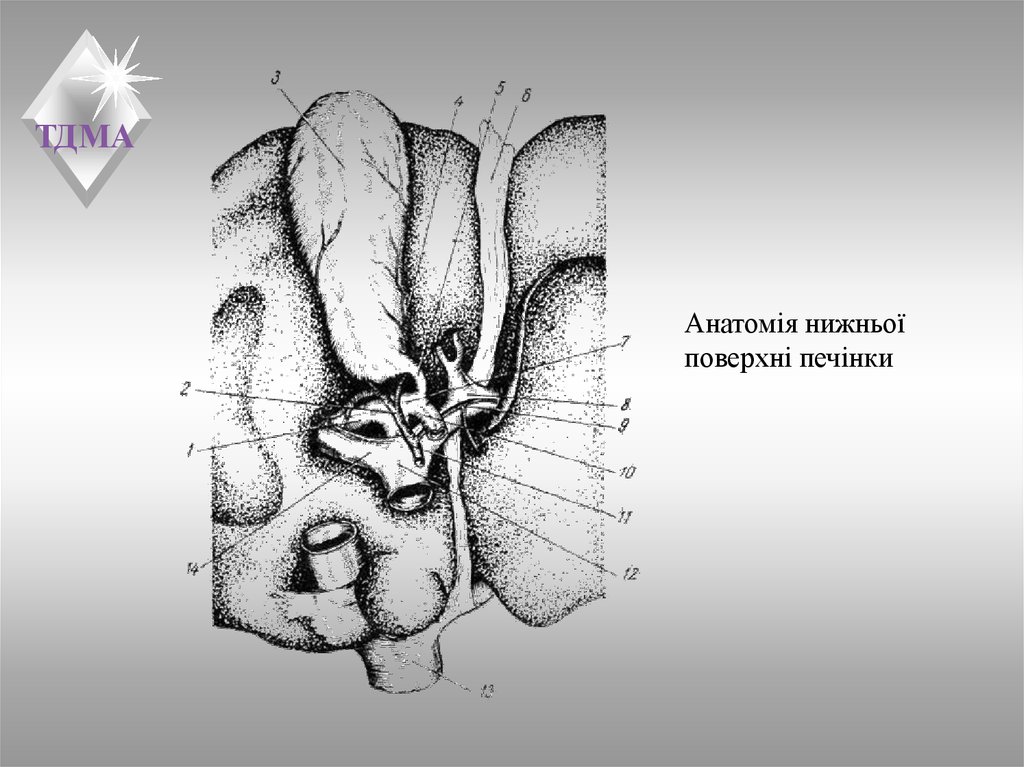

Анатомия и особенности Гартманова кармана желчного пузыря